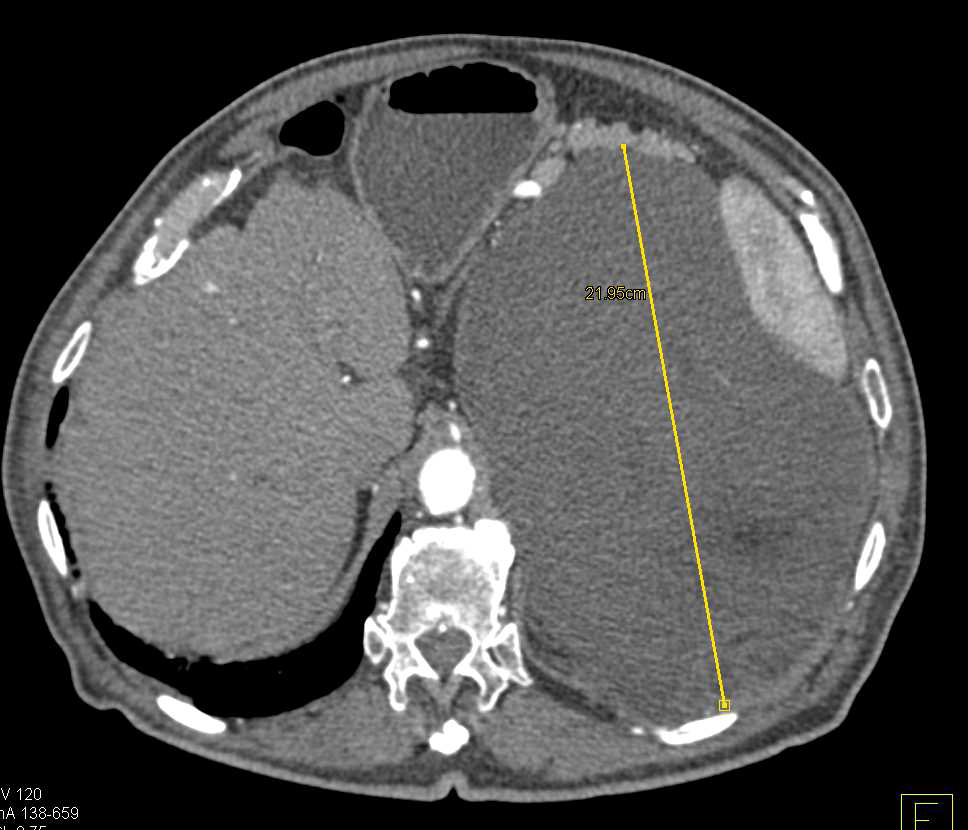

retroperitoneal liposarcoma spleen bloc resection stomach medially laterally abdomen surgical displacing pelvis cureus

liposarcoma retroperitoneal ct abdominal figure mass giant contrast left literature management case report review ol abdomen publications spandidos